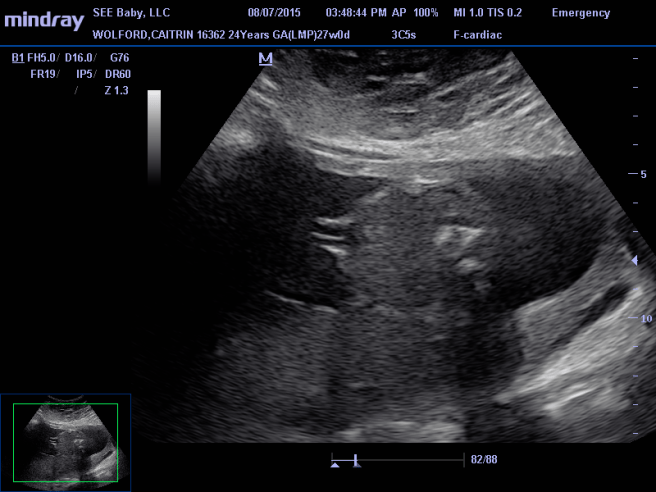

11220846_909770215751106_2957804900740871137_n

Side view with her head instead of her legs. Face is really blurry. Top blob is a picture of her arm that is kind of cut in half. It’s a view of her muscle and bone inside the middle of her arm.